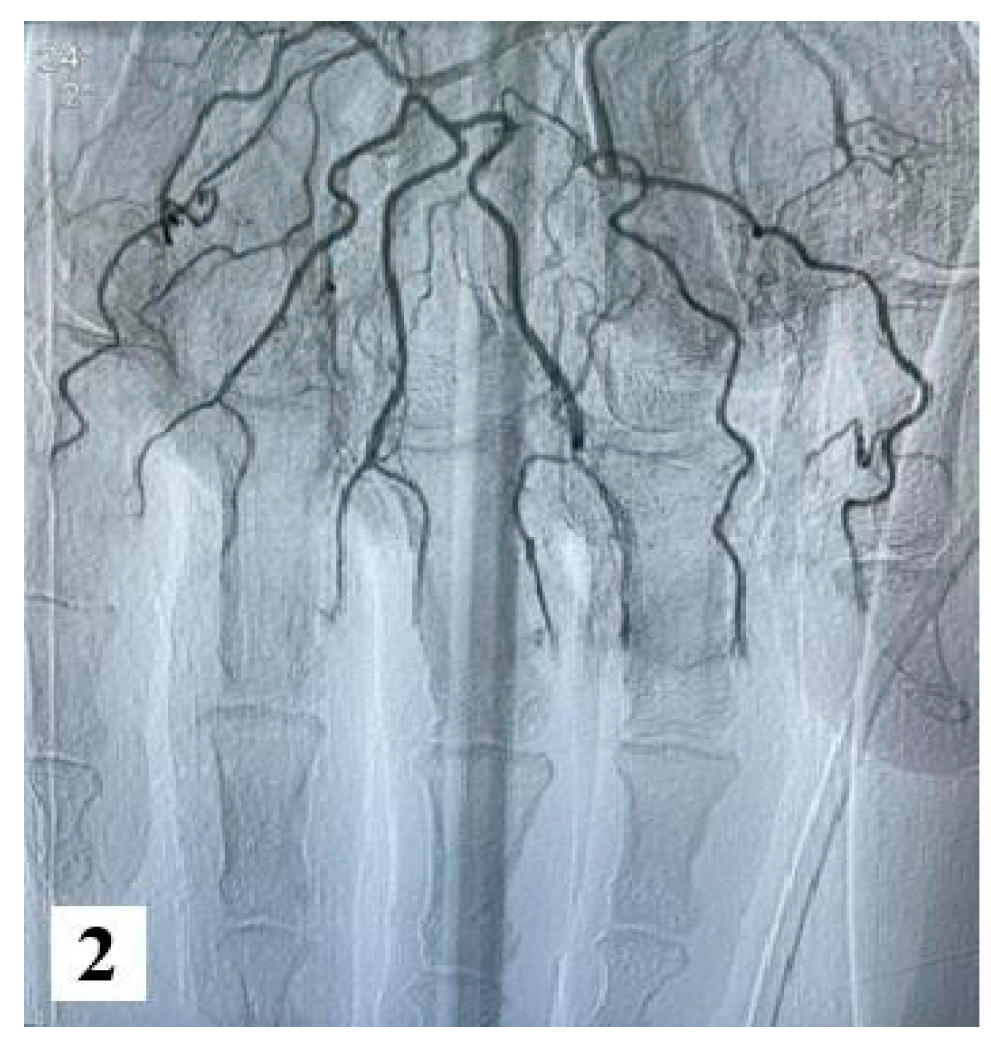

Furthermore, an angiography of the upper limb indicated the absence of vascularization at the level of bilateral proximal phalanges. The brachial, radial, and ulnar arteries were found to be patent, exhibiting a normal appearance.

Figure 2.

Angiography images (from hospital archive) (part 1).